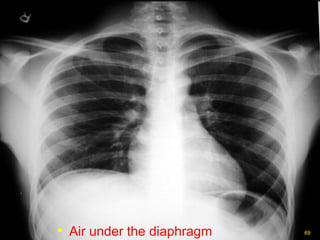

Free air Free air beneath diaphragm

Air under the diaphragm